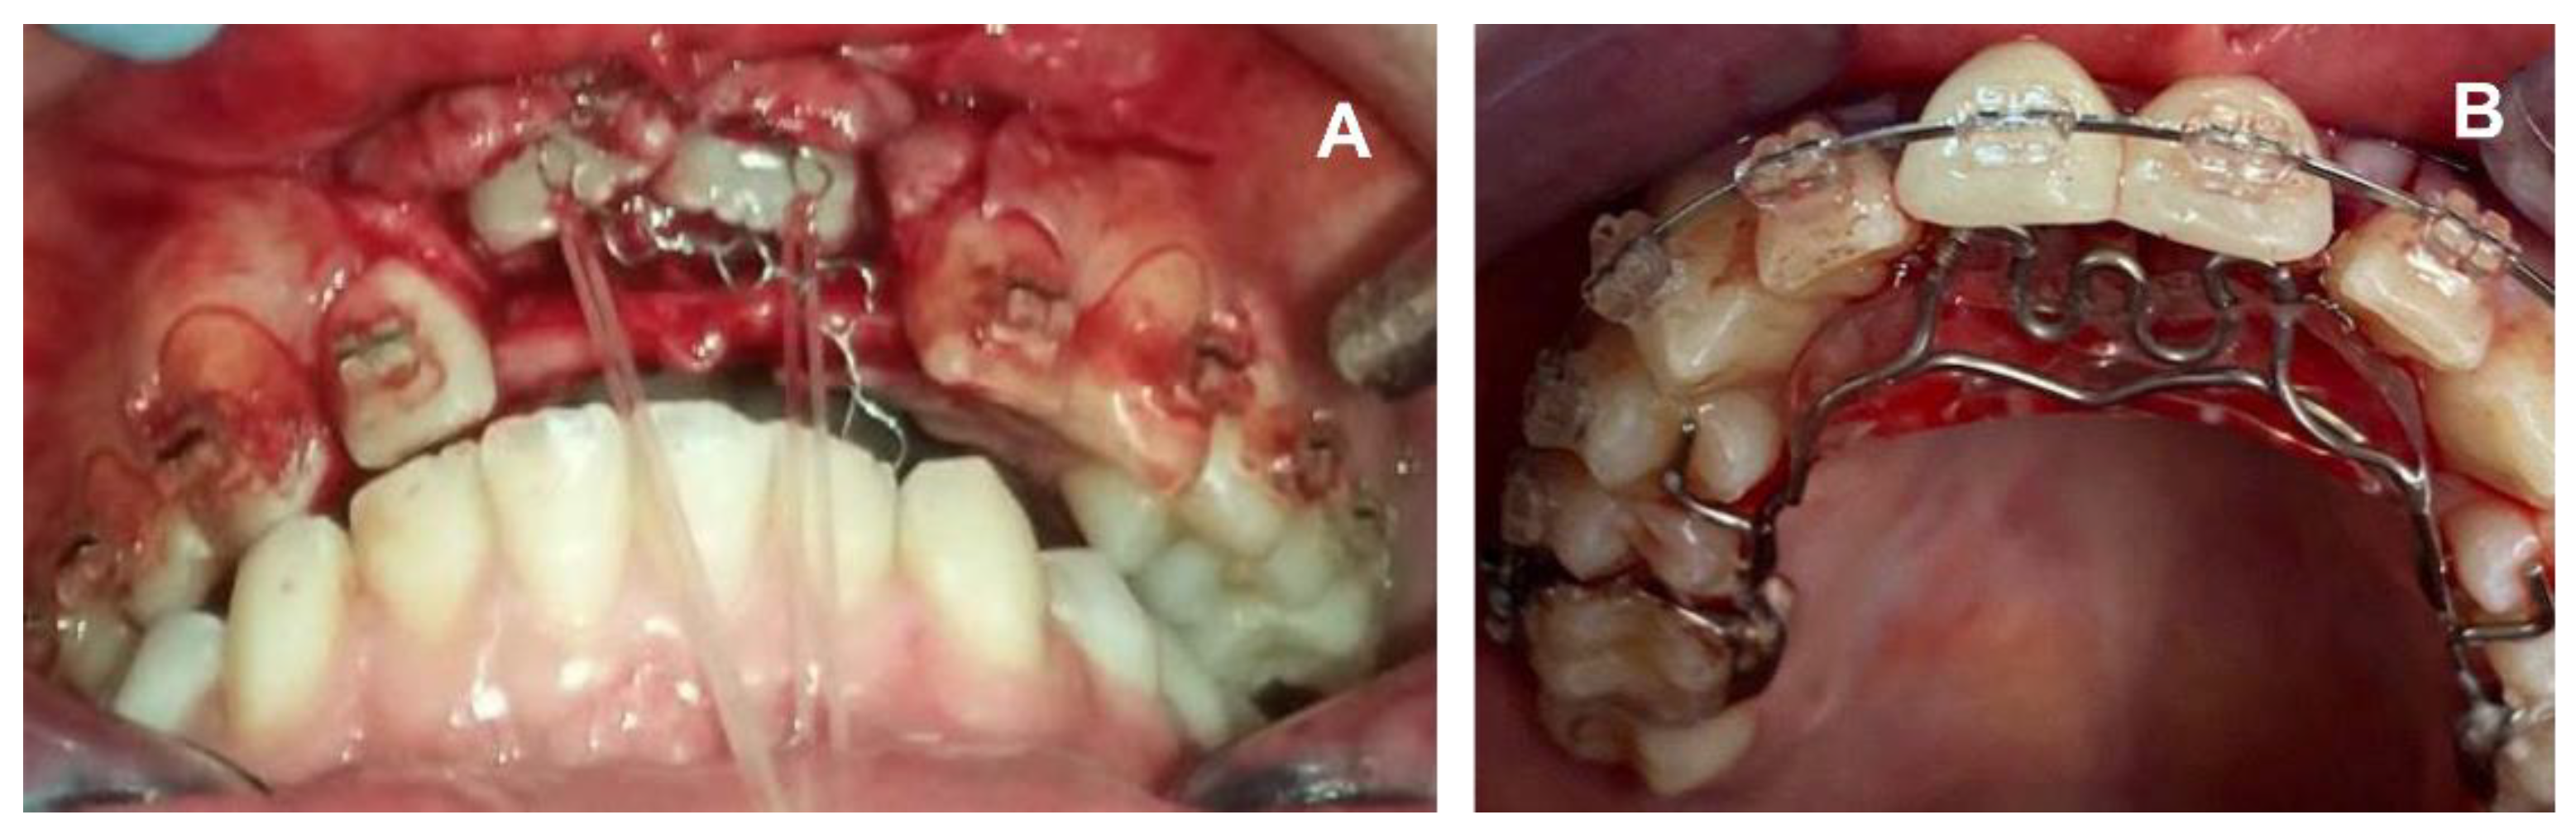

2. Case Report

2.2. Clinical Exams and Diagnosis

2.3. Therapeutic Plan

3. Results